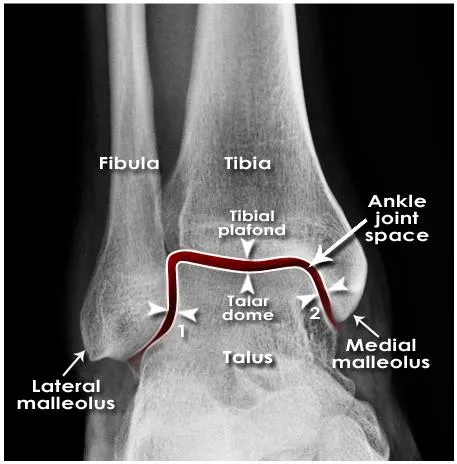

B. Mortise X-Ray

Taken with ankle in 15-25 degrees of internal rotation

Useful in evaluation of articular surface between talar dome and mortise

Tibio-fibula overlap about 1 mm

Tibiofibular clear space < 6 mm

Medical clear space < 4 mm

Medial clear space

Between lateral border of medial malleous and medial talus

<4mm is normal

4mm suggests lateral shift of talus

Medial clear space : lateral malleolar Fx. or Deltoid diosruption